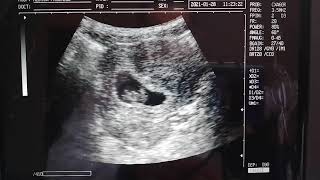

Embrión Más Pequeño 8 Semanas, EMBARAZO DE 8 SEMANAS EMBRIÓN DE 1.6 cm, 13.18 MB, 09:36, 14,000, Dr.Bernardo Velasco, 2021-11-16T18:03:43.000000Z, 3, Foetus At 8 Weeks Photograph by Sciepro/science Photo Library | Fine, fineartamerica.com, 900 x 900, jpeg, WebEl desarrollo de tu bebé. Esta semana los dedos de las manos y los pies de tu bebé ya empiezan a notarse, los párpados casi le cubren los ojos, desde su garganta se extienden los tubos respiratorios hasta sus pulmones en desarrollo, y su "colita" embriónica está. WebEl tamaño del embrión con 8 semanas de embarazo es de unos 13-18 milímetros y puede pesar unos 3 gramos. Un cambio muy importante que sucede en la. WebEmbrión más pequeño que edad gestacional: Hola a todas, Hoy fuimos a hacernos nuestra primera eco de 8 semanas y hemos escuchado y visto el. WebSemana 8 de embarazo: desarrollo del bebé. Esta semana aparecerán pequeños dedos en las manos y los pies de tu pequeño. Además, podrá flexionar los brazos a la altura de., 20, embrion-mas-pequeno-8-semanas, Novedades y Muebles WebEl desarrollo de tu bebé. Esta semana los dedos de las manos y los pies de tu bebé ya empiezan a notarse, los párpados casi le cubren los ojos, desde su garganta se extienden los tubos respiratorios hasta sus pulmones en desarrollo, y su "colita" embriónica está. WebEl tamaño del embrión con 8 semanas de embarazo es de unos 13-18 milímetros y puede pesar unos 3 gramos. Un cambio muy importante que sucede en la. WebEmbrión más pequeño que edad gestacional: Hola a todas, Hoy fuimos a hacernos nuestra primera eco de 8 semanas y hemos escuchado y visto el. WebSemana 8 de embarazo: desarrollo del bebé. Esta semana aparecerán pequeños dedos en las manos y los pies de tu pequeño. Además, podrá flexionar los brazos a la altura de.

WebEn un embarazo de 8 semanas, el embrión tiene una longitud de 13 milímetros desde la coronilla hasta las nalgas. Su cabeza poco a poco comienza a tomar forma, de modo.

WebTu embrión en crecimiento a las 8 semanas. Estás a las 8 semanas, ¡Hurra! Sólo faltan dos semanas para que estés en los dos dígitos. Bien, ahora su bebé mide 0.63″ y pesa 0.04. WebUna ecografía a las 8 semanas de embarazo muestra que el embrión es un pequeño astronauta flotando en el espacio. En esta coyuntura tiene el tamaño de un arándano (8. WebEstamos embaradados de 8 semanas (según lo que nos dijo el médico), pero el viernes pasado fuimos a una revisión normal y nos dijo que el embrión está mas pequeño de lo. WebSemana 8: Desarrollo del bebé. En la semana 8 el embrión mide aproximadamente 16 milímetros de tamaño. A partir del final de esta semana, incluso se pueden ver los. WebPequeño para la edad gestacional. Significa que un feto o un bebé es más pequeño o está menos desarrollado de lo normal para su sexo y edad gestacional. La edad gestacional. WebLos índices de tamaño del embrión a las 8 semanas ya son "impresionantes" y tienen aproximadamente 4 cm. Es el final del segundo mes de gestación que se caracteriza por. WebA las 8 semanas ya se ve el embrión en la ecografía. A menudo, la edad a la que la paciente cree que está embarazada no coincide con la edad del embarazo observada en.

WebEl embrión a las 8 semanas de embarazo tiene una edad de 6 semanas desde que se produjo la fecundación. La longitud desde la coronilla a las nalgas ronda los 15-20. WebSi en la ecografia el embrion es de ocho semanas debe de tener latido pero si el embrion es de menor tamaño puede ser que no tenga latido.Para ver la evolución del embarazo. Webmellizos. un embrión más pequeño que otro. necesito ayuda: embrion más pequeño de lo normal. embrión pequeño 6 semanas. implantación tardía, embrión mas.

WebLos índices de tamaño del embrión a las 8 semanas ya son "impresionantes" y tienen aproximadamente 4 cm. Es el final del segundo mes de gestación que se caracteriza por. WebA las 8 semanas ya se ve el embrión en la ecografía. A menudo, la edad a la que la paciente cree que está embarazada no coincide con la edad del embarazo observada en. WebYa tienes 8 semanas de embarazo, el corazón de tu bebé late fuerte y comienzas a sentir algunos cambios en tu cuerpo. El desarrollo de tu bebé. Mide entre 1,5 y 2 cm. (0,59 y.